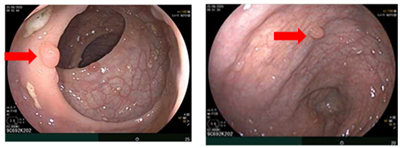

UNG THƯ DẠ DÀY KHỞI PHÁT SỚM

Theo Globocan 2022, ung thư dạ dày đứng thứ 5 về tỷ lệ mắc và tỷ lệ tử vong, với 968 784 ca mắc mới và 660 175 ca tử vong. Bệnh tiến triển thầm lặng, các triệu chứng ban đầu  thường mơ hồ và không đặc hiệu dễ nhầm lẫn với các bệnh lành...